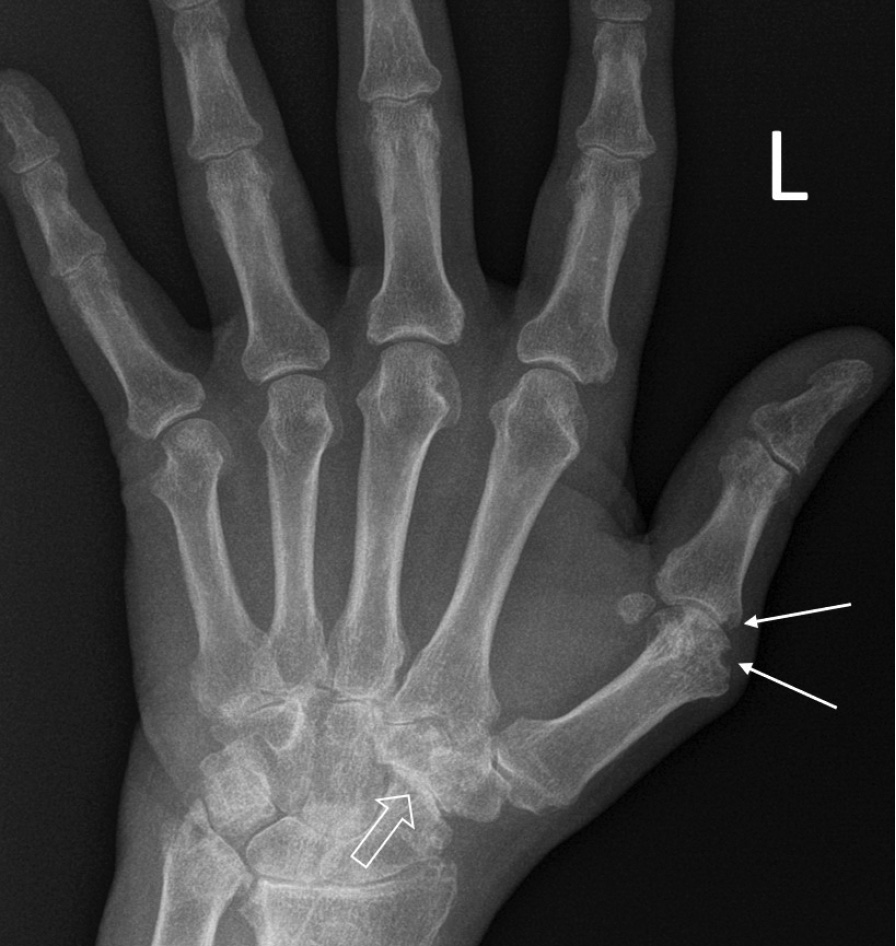

При компьютерной томографии органов грудной клетки данных за «свежие» очаговые и инфильтративные изменения не получено. Увеличения лимфатических узлов подмышечных областей, средостения, корней легких не выявлено. Отмечался усиленный грудной кифоз, обызвествление передней продольной связки, на всем уровне исследования определялись передне-боковые спондилофиты, а также анкилоз большинства реберно-поперечных суставов. По данным рентгенографии кистей (рис. 1, 2) и стоп (рис. 3, 4) диагностированы признаки эрозивного артрита, анкилоз суставов запястья. По данным МРТ крестцово-подвздошных суставов (КПС) определялся неравномерный анкилоз КПС, хрящи по суставным поверхностям неравномерной толщины, примерно на половине протяжении сустава отсутствуют, «суставной промежуток» облитерирован. Неравномерность и нечеткость контура суставных поверхностей за счет множества краевых эрозий справа, единичных – слева, с наличием остеокластоза, в нижнем отделе слева по смежным отделам определяются участки трабекулярного отека, данная находка клинически интерпретирована как двусторонний активный сакроилиит (рис. 5, 6).

Рис. 1. Рентгенограмма левой кисти в прямой проекции. Краевые эрозии суставных поверхностей первого пястно-фалангового сустава (тонкие стрелки), сужение суставных щелей суставов запястья с формированием анкилозов (толстая стрелка)

Рис. 2. Рентгенограмма правой кисти в прямой проекции. Краевая эрозия суставной поверхности лучевой кости (тонкая стрелка), множественные анкилозы суставов запястья (толстые стрелки)